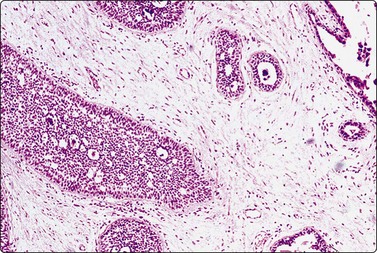

image image

Fig. 7.15 Regenerative epithelial atypia in mastitis

(A) Atypical, reactive/regenerating epithelial cells with a background of histiocytes, inflammatory cells and debris (MGG, HP); (B) Corresponding tissue section (H&E, IP).

There are four types of mastitis recognized; acute, chronic, granulomatous and non-specific.93 The diagnosis of acute mastitis and abscess presents no problems. Pregnancy is the most common association, but occasionally cysts become infected (often by coagulase-negative staphylococci). The entity of subareolar abscess is recognized separately (Fig. 7.16). Chronic mastitis may be the result of persistence of an acute mastitis, a reaction to retained secretion in fibrocystic disease or duct ectasia, or secondary to previous surgery.